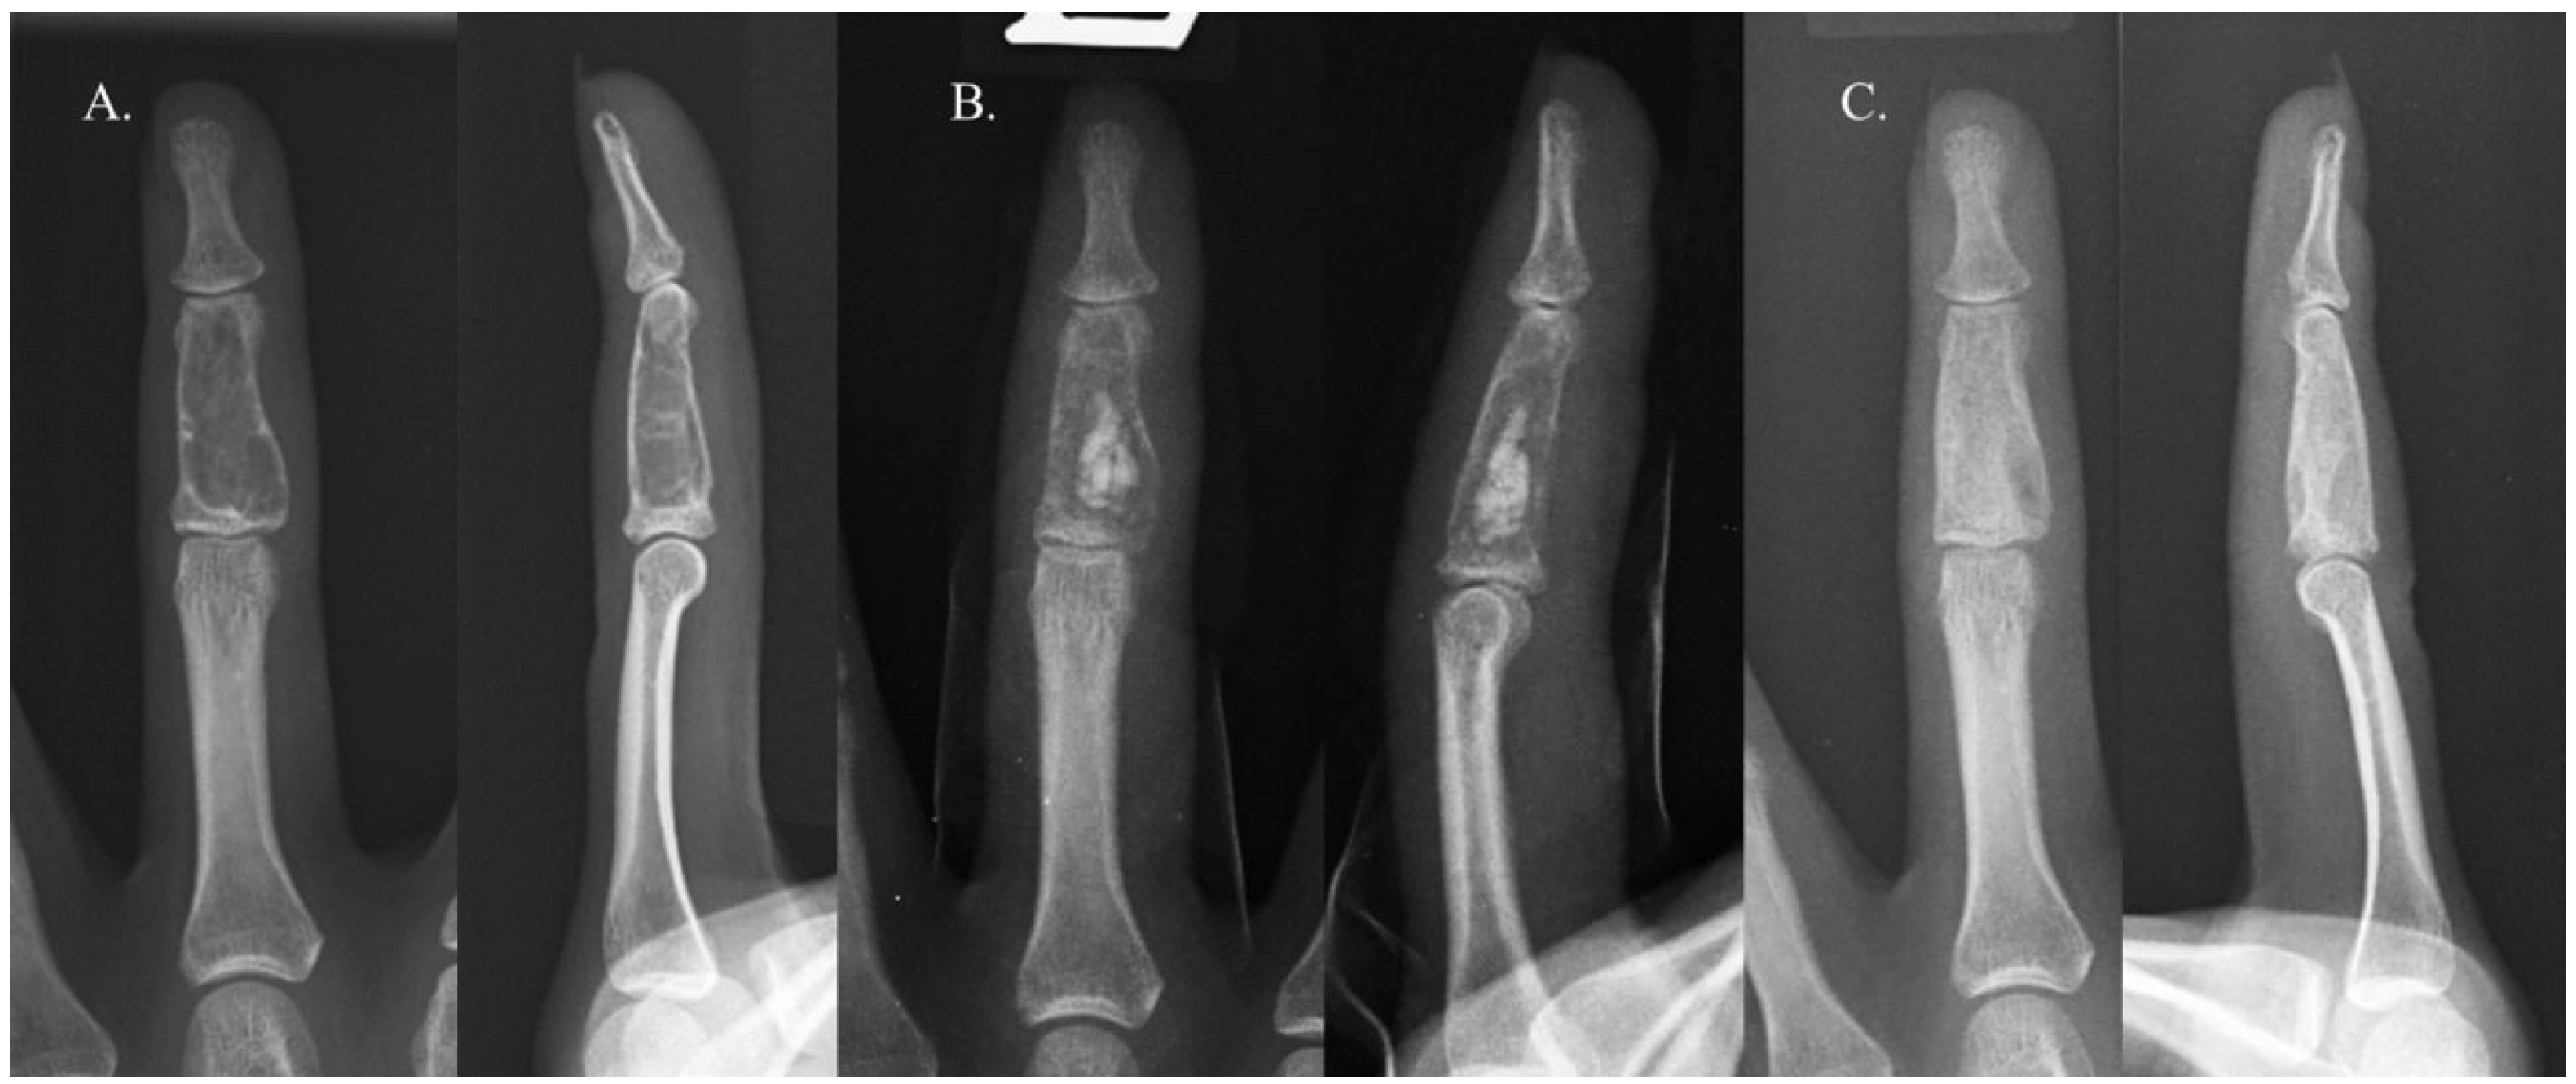

2.1. Surgical Procedure and Rehabilitation

2.2. Radiographic Evaluation